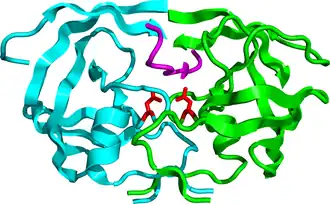

HIV-1 protease dimer in white and grey, with peptide substrate in black and active site aspartate side chains in red. (PDB: 1KJF) | |||||||||

Mature HIV protease exists as a 22 kDa homodimer, with each subunit made up of 99 amino acids.[1] A single active site lies between the identical subunits and has the characteristic Asp-Thr-Gly (Asp25, Thr26 and Gly27) catalytic triad sequence common to aspartic proteases.[8] As HIV-1 PR can only function as a dimer, the mature protease contains two Asp25 amino acids, one from each monomer, that act in conjunction with each other as the catalytic residues.[9] Additionally, HIV protease has two molecular "flaps" which move a distance of up to 7 Å when the enzyme becomes associated with a substrate.[10] This can be visualized with animations of the flaps opening and closing.

With its integral role in HIV replication, HIV protease has been a prime target for drug therapy. HIV protease inhibitors work by specifically binding to the active site by mimicking the tetrahedral intermediate of its substrate and essentially becoming “stuck,” disabling the enzyme. After assembly and budding, viral particles lacking active protease cannot mature into infectious virions. Several protease inhibitors have been licensed for HIV therapy.[19]